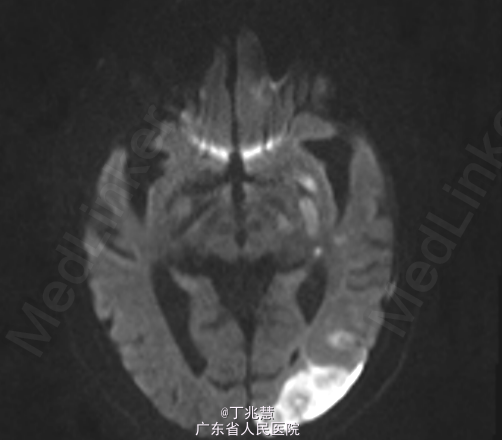

女性,46岁。因“反复发热、头痛2月”入院。患者自2个月前无明显诱因出现头痛,呈持续性,起病初期头痛程度轻,可忍受,自服药治疗(具体用药不详)病情未见好转,且头痛程度逐步加重,难以忍受,无恶心,呕吐,无肢体抽搐,间中有发热,体温最高可达39.2摄氏度。 既往糖尿病史5年,控制不佳。

查体:心肺腹查体未见异常。神经专科:右侧上下肢肌力0级左侧上下肢体肌力5级。 颈强直,颏胸距4横指,双侧Kernig征(+)。

诊断:结核性脑膜脑炎; 治疗:抗结核治疗。

随访:患者转胸科医院进一步治疗,具体不详; 讨论:结核菌一般侵犯脑膜多见,较少累及大脑实质,本例患者累及脑实质,有肢体无力表现。经规律抗结核治疗后预后相对良好。